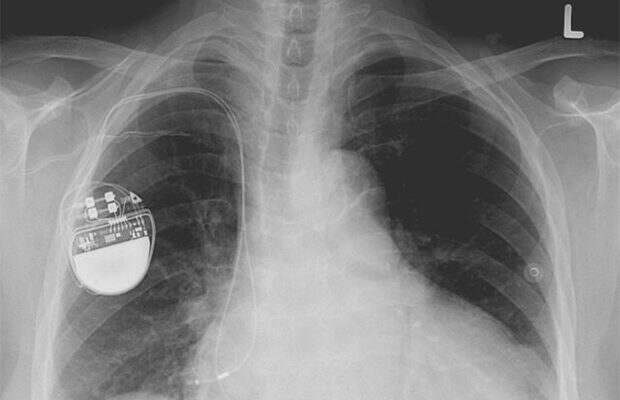

Кардиостимулятор

Уилсон Грейтбатч совершил классическую ошибку – вытащил из коробки не ту деталь. Так на свет появился прибор, который спас жизни миллионов людей. В 1956 г. Грейтбатч работал над созданием прибора записи сердечного ритма животных в университете Буффало. Он полез в ящик стола и достал резистор неправильного размера, подключив его к цепи. Когда ученый включил прибор, то услышал ритмичный звук, который напоминал биение человеческого сердца. Сегодня более чем полмиллиона кардиостимуляторов имплантируются каждый год.